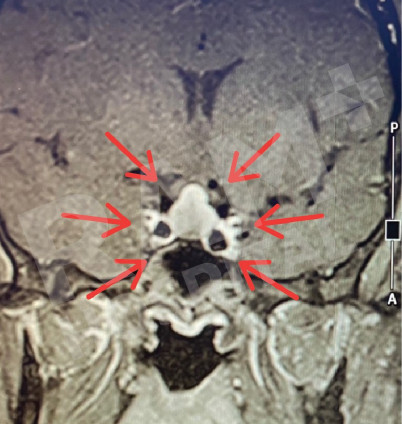

磁共振成像(MRI)可清晰、细致地显示垂体的异常病变,精准定位垂体腺瘤的位置;结合静脉造影增强检查,还能明确腺瘤的具体位置与病变性质,同时清晰呈现脑部周边组织及鼻窦的情况。这一项检查结果可为制定诊疗方案、随访评估垂体腺瘤的治疗效果,乃至规划手术方案提供明确、可靠的依据。

| 术前 | 术后 |